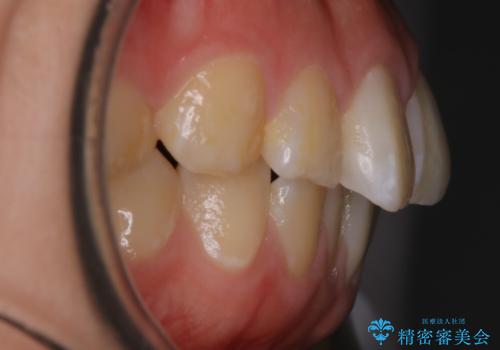

【非抜歯】ガタつきと歯軸を正して長持ちする歯へ

- 歯のガタつきと噛み合わせの改善を主訴に来院されました。

非抜歯で、少量の奥歯の移動と歯列の拡大・IPRを駆使して主訴を改善するための治療計画を立案しました。